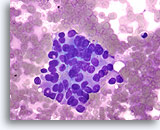

Lobulair neoplasie, Borst FNA, Celblok.

Een in-situ groeipatroon van lobulaire neoplasie is moeilijk of onmogelijk te identificeren in cytologische preparaten. Deze cluster van ongeveer 5 trossen is gedeeltelijk opgezet door het kenmerkende patroon van een losse ‘zak knikkers’ van lobulaire neoplasie zonder vorming van een glandulair lumen.

40X

Lobulair neoplasie, Borst FNA, Celblok.

Een in-situ groeipatroon van lobulaire neoplasie is moeilijk of onmogelijk te identificeren in cytologische preparaten. Deze cluster van ongeveer 5 trossen is gedeeltelijk opgezet door het kenmerkende patroon van een losse ‘zak knikkers’ van lobulaire neoplasie zonder vorming van een glandulair lumen.

40X

Lobulair neoplasie, Borst FNA, Celblok.

Een sterkere vergroting toont een kenmerkende targetoïde cytoplasmische vacuole (pijl)

100X

Lobulair neoplasie, Borst FNA, Celblok.

Een sterkere vergroting toont een kenmerkende targetoïde cytoplasmische vacuole (pijl)

100X